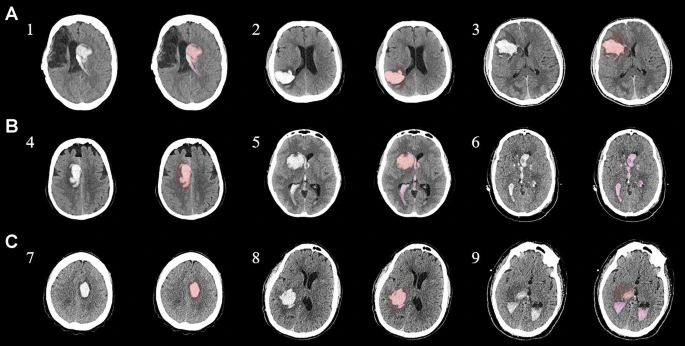

圖1:每個(gè)間充質(zhì)干細(xì)胞治療患者按組的原始非對(duì)比計(jì)算機(jī)斷層掃描和分割結(jié)果

本研究納入2018年1月1日至2020年10月31日發(fā)病168小時(shí)內(nèi)發(fā)生急性ICH的患者。間充質(zhì)干細(xì)胞被靜脈注射給9名患者(5名女性,4名男性),平均年齡(范圍)為61(36-84)歲。表1總結(jié)了人口統(tǒng)計(jì)學(xué)和臨床??特征 。出于描述目的,患者按照入組順序獲得編號(hào),并連續(xù)分配到三組中的一組,每組三人。根據(jù)模型 2 分割,ICH體積范圍為0.1至54.9mL(平均ICH體積為23.5mL)。5例ICH累及局部腦葉,其余則位于基底節(jié)或外囊深處。在三名患者中,ICH位于丘腦(圖1),在一名患者中,血腫位于多個(gè)腦結(jié)構(gòu)(即尾狀核、殼核和蒼白球)。平均而言,MSC在ICH后3天進(jìn)行注射。